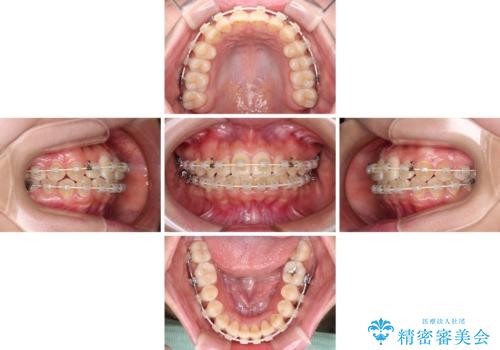

- 矯正装置

- 審美装置

治療前にお伝えした治療期間は1~1年半でして、1年4か月の期間で終えることができました。

ワイヤー矯正は見た目や装置が当たることでの痛みを気にされる方が多いですが、月1回来院して処置をしてもらうだけで歯並びが整うため、大変お勧めです。